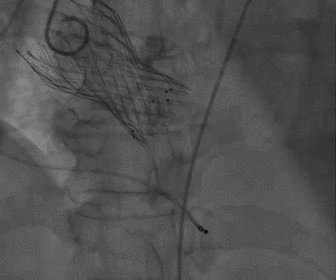

根部造影

球囊预扩

胶囊腔定位

瓣膜释放

造影观察瓣膜形态